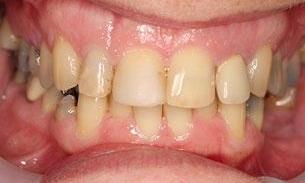

This young dad had four congenitally missing upper teeth. He had a quick orthodontic treatment and a large span bridge placed in as a teenager. He never smiles with teeth showing.

After many years of wear and tear, some of the work started to break and fail. We removed the defective bridges, managed to save all the existing teeth and placed four implant supported crowns in. The patient is very happy to be able to smile confidently now.